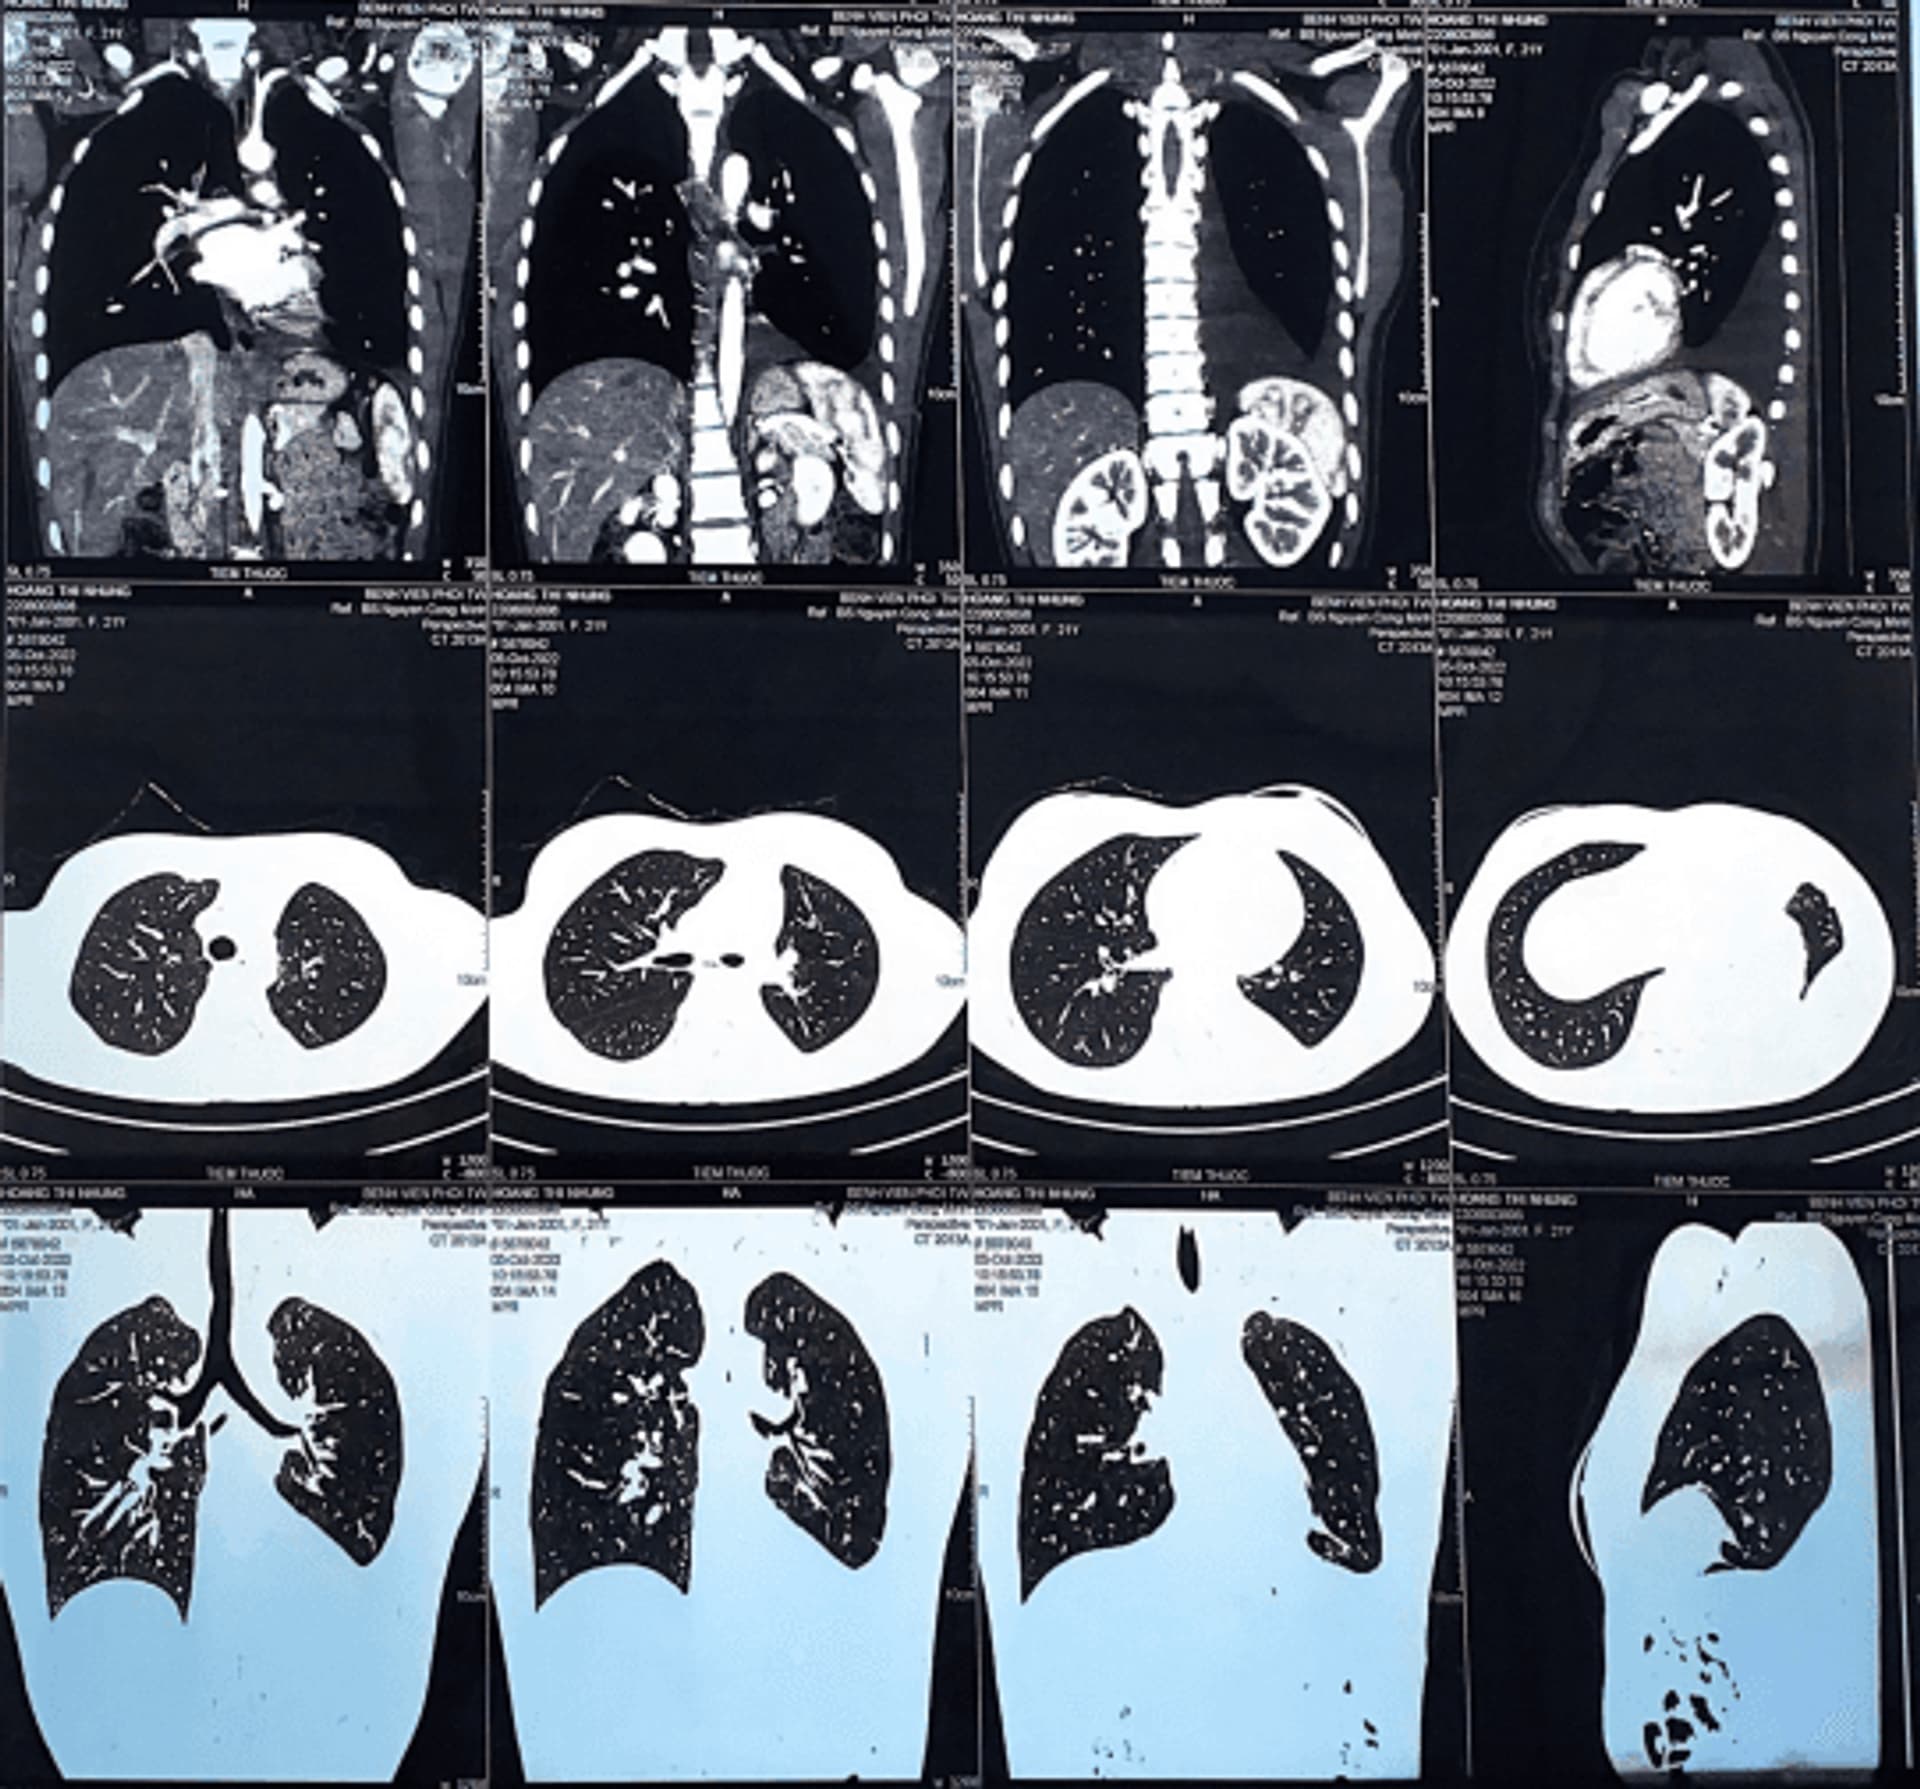

Sau hai tuần từ lúc có chẩn đoán bệnh nhân được tiến hành phẫu thuật điều trị bệnh, TS. BSCC Đinh Văn Lượng, Giám đốc Bệnh viện trực tiếp phẫu thuật. Cuộc phẫu thuật diễn ra thuận lợi và thành công, bệnh nhân đã được cắt thùy dưới phổi trái chứa u và vét hạch triệt căn nhóm 5-6, 7, 9, 10, 11; bệnh nhân hồi phục rất tốt, sau mổ bảy ngày đã rút được sonde dẫn lưu, không đau và ăn uống được, vận động bình thường, bác sỹ cho ra viện về nhà nghỉ ngơi hồi phục sức khỏe.

Sau 2 tuần nghỉ ngơi hồi phục sức khỏe tại nhà, bệnh nhân quay lại Bệnh viện tái khám. Bác sỹ Minh, khoa Ung Bướu 2 cho biết “Khi bệnh nhân quay lại tái khám theo hẹn thấy bệnh nhân tăng cân, sức khỏe cải thiện, các triệu chứng bệnh thuyên giảm, tình thần bệnh nhân và người nhà phấn chấn mang lại cho các y bác sĩ rất nhiều niềm vui, đặc biệt với trường hợp bệnh nhân N mới chỉ có 21 tuổi, còn chưa có gia đình”. Sau khi đánh giá tổng thể bệnh, các bác sỹ khoa Ung Bướu 2 đã cho bệnh nhân truyền hóa chất bổ trợ 4 chu kỳ nhằm tăng hiệu quả điều trị, giảm nguy cơ tái phát sớm cho người bệnh. Hiện tại, N vẫn tái khám đều đặn theo hẹn tại Khoa Ung Bướu 2 – Bệnh viện Phổi Trung ương sức khỏe ổn định và đã có công việc mới tại Việt Nam, tinh thần bệnh nhân và người nhà vui vẻ phấn chấn.